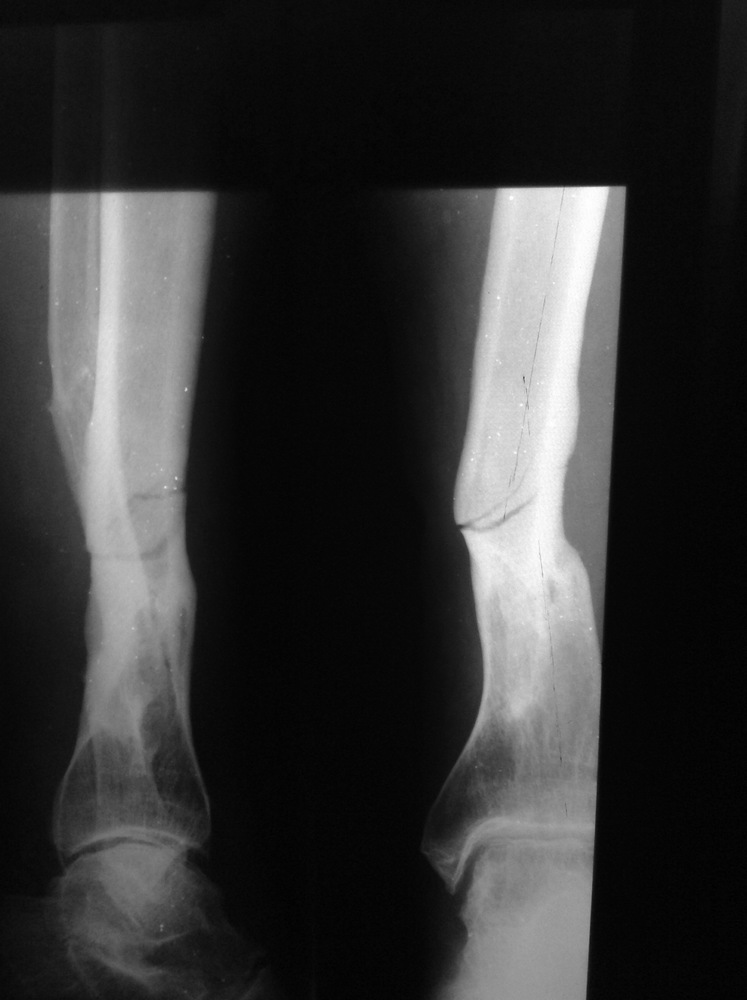

Здравствуйте. Прошу помощи участников форума. Обратился мужчина 55 лет. Травма в марте этого года: на ногу упало бревно. Лечение в гипсовой повязке.

Сентябрь 2015

март 2015

На данный момент ходит самостоятельно с тростью и в ортезе с шинами и замками. Боли нет. Может наступать на ногу и без ортеза - боли также не испытывает. Пальпация в области перелома безболезненна. Последняя рентгенограмма от 22.09.2015 - прослеживается линия перелома.

В анамнезе: 30 лет назад уже имел место открытый перелом костей голени, осложнившийся развитием инфекции - проводили лечение в АВФ. С тех пор и до марта этого года конечность не беспокоила. Курит.

Прошу помочь с выбором тактики ведения. Есть опасения, что если отпустить его с полной нагрузкой, рано или поздно произойдет перелом - вопрос решится сам собой в пользу БИОСа. Имеет ли смысл выполнять его сейчас, превентивно/с лечебной целью? Как расценить ситуацию: несращение, сращение, как назвать, вообще?Спасибо.